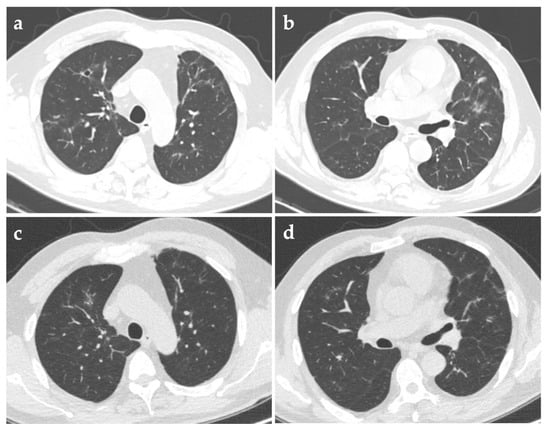

Three months after discharge, repeated chest CT in the follow-up visit showed that the solid nodules shrunk significantly and most of the cavities vanished. Half a year after discharge, another CT scan showed only several solid micronodules and some irregular linear opacities, without any cavities (Figure 3). Maintenance therapy with amoxicillin-clavulanate was then discontinued.

Figure 3. Repeated computed tomography (CT) images three months (a,b) and six months (c,d) after discharge, showing a significant reduction in both nodules and cavities.